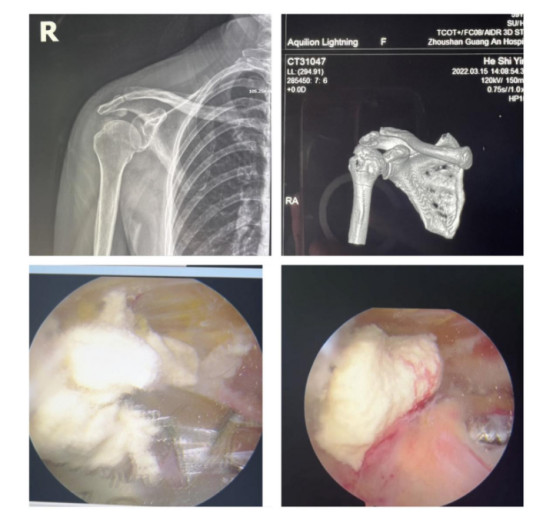

賀大媽慕名來廣安醫(yī)院找羅軍主任就診,面對羅醫(yī)生,賀大媽哭訴:“羅醫(yī)生,我真想剁下自己的這只胳膊。”羅軍主任根據(jù)患者的癥狀拍片,診斷為岡上肌鈣化性肌腱炎,隨后,羅醫(yī)生為李大媽進行了肩關(guān)節(jié)鏡微創(chuàng)手術(shù),竟從她的右肩“擠”出“牙膏”。

鈣化性肌腱炎是一種自限性疾病,就是疾病發(fā)生發(fā)展到一定程度后,經(jīng)長期機體調(diào)節(jié)能夠控制病情發(fā)展并逐漸恢復(fù)痊愈。它分為四個階段:鈣化前期、鈣化形成期、鈣化吸收期、鈣化后期,往往在“鈣鹽斑塊”吸收時,疼痛最劇烈,賀大媽就正處于“吸收期”。